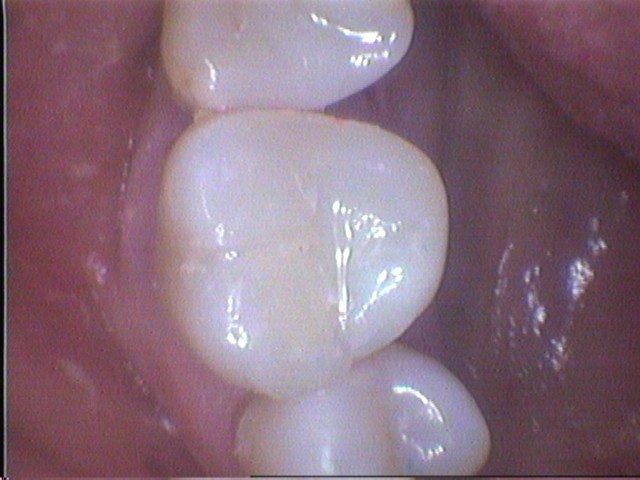

The tooth is then rebuilt using modern high wearing composite filling material. This Gloucester patient was delighted with the final result.